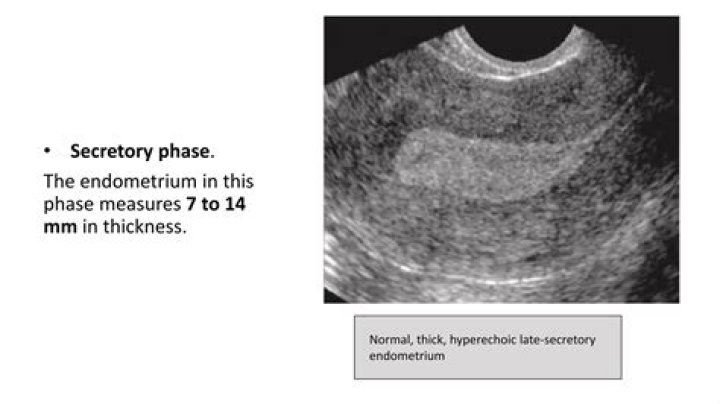

The progesterone surge of ovulation ends the proliferative phase, and the endometrium moves into the secretory (or luteal phase) of development. Under normal conditions the secretory phase is 14 days in length, and the endometrium moves through an orderly sequence of morphologic changes (Fig. 10.2).

The secretory phase of the uterine cycle begins at ovulation. In this phase, the glands become even more complexly coiled and the endometrial lining reaches its maximal thickness, whereas the stratum basalis and myometrium remain relatively unchanged.